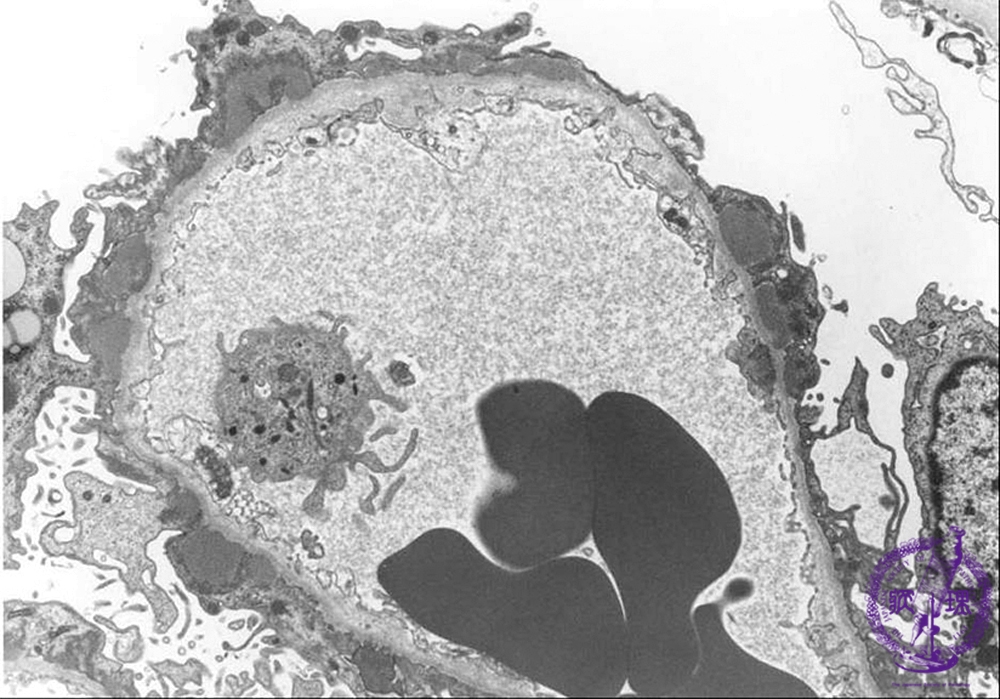

- ★(2)Membranous nephropathy

Electron microscopic findings: Stage I: Subepithelial electron dense deposits are observed (red arrows). The basement membrane is not thickened(blue arrows).